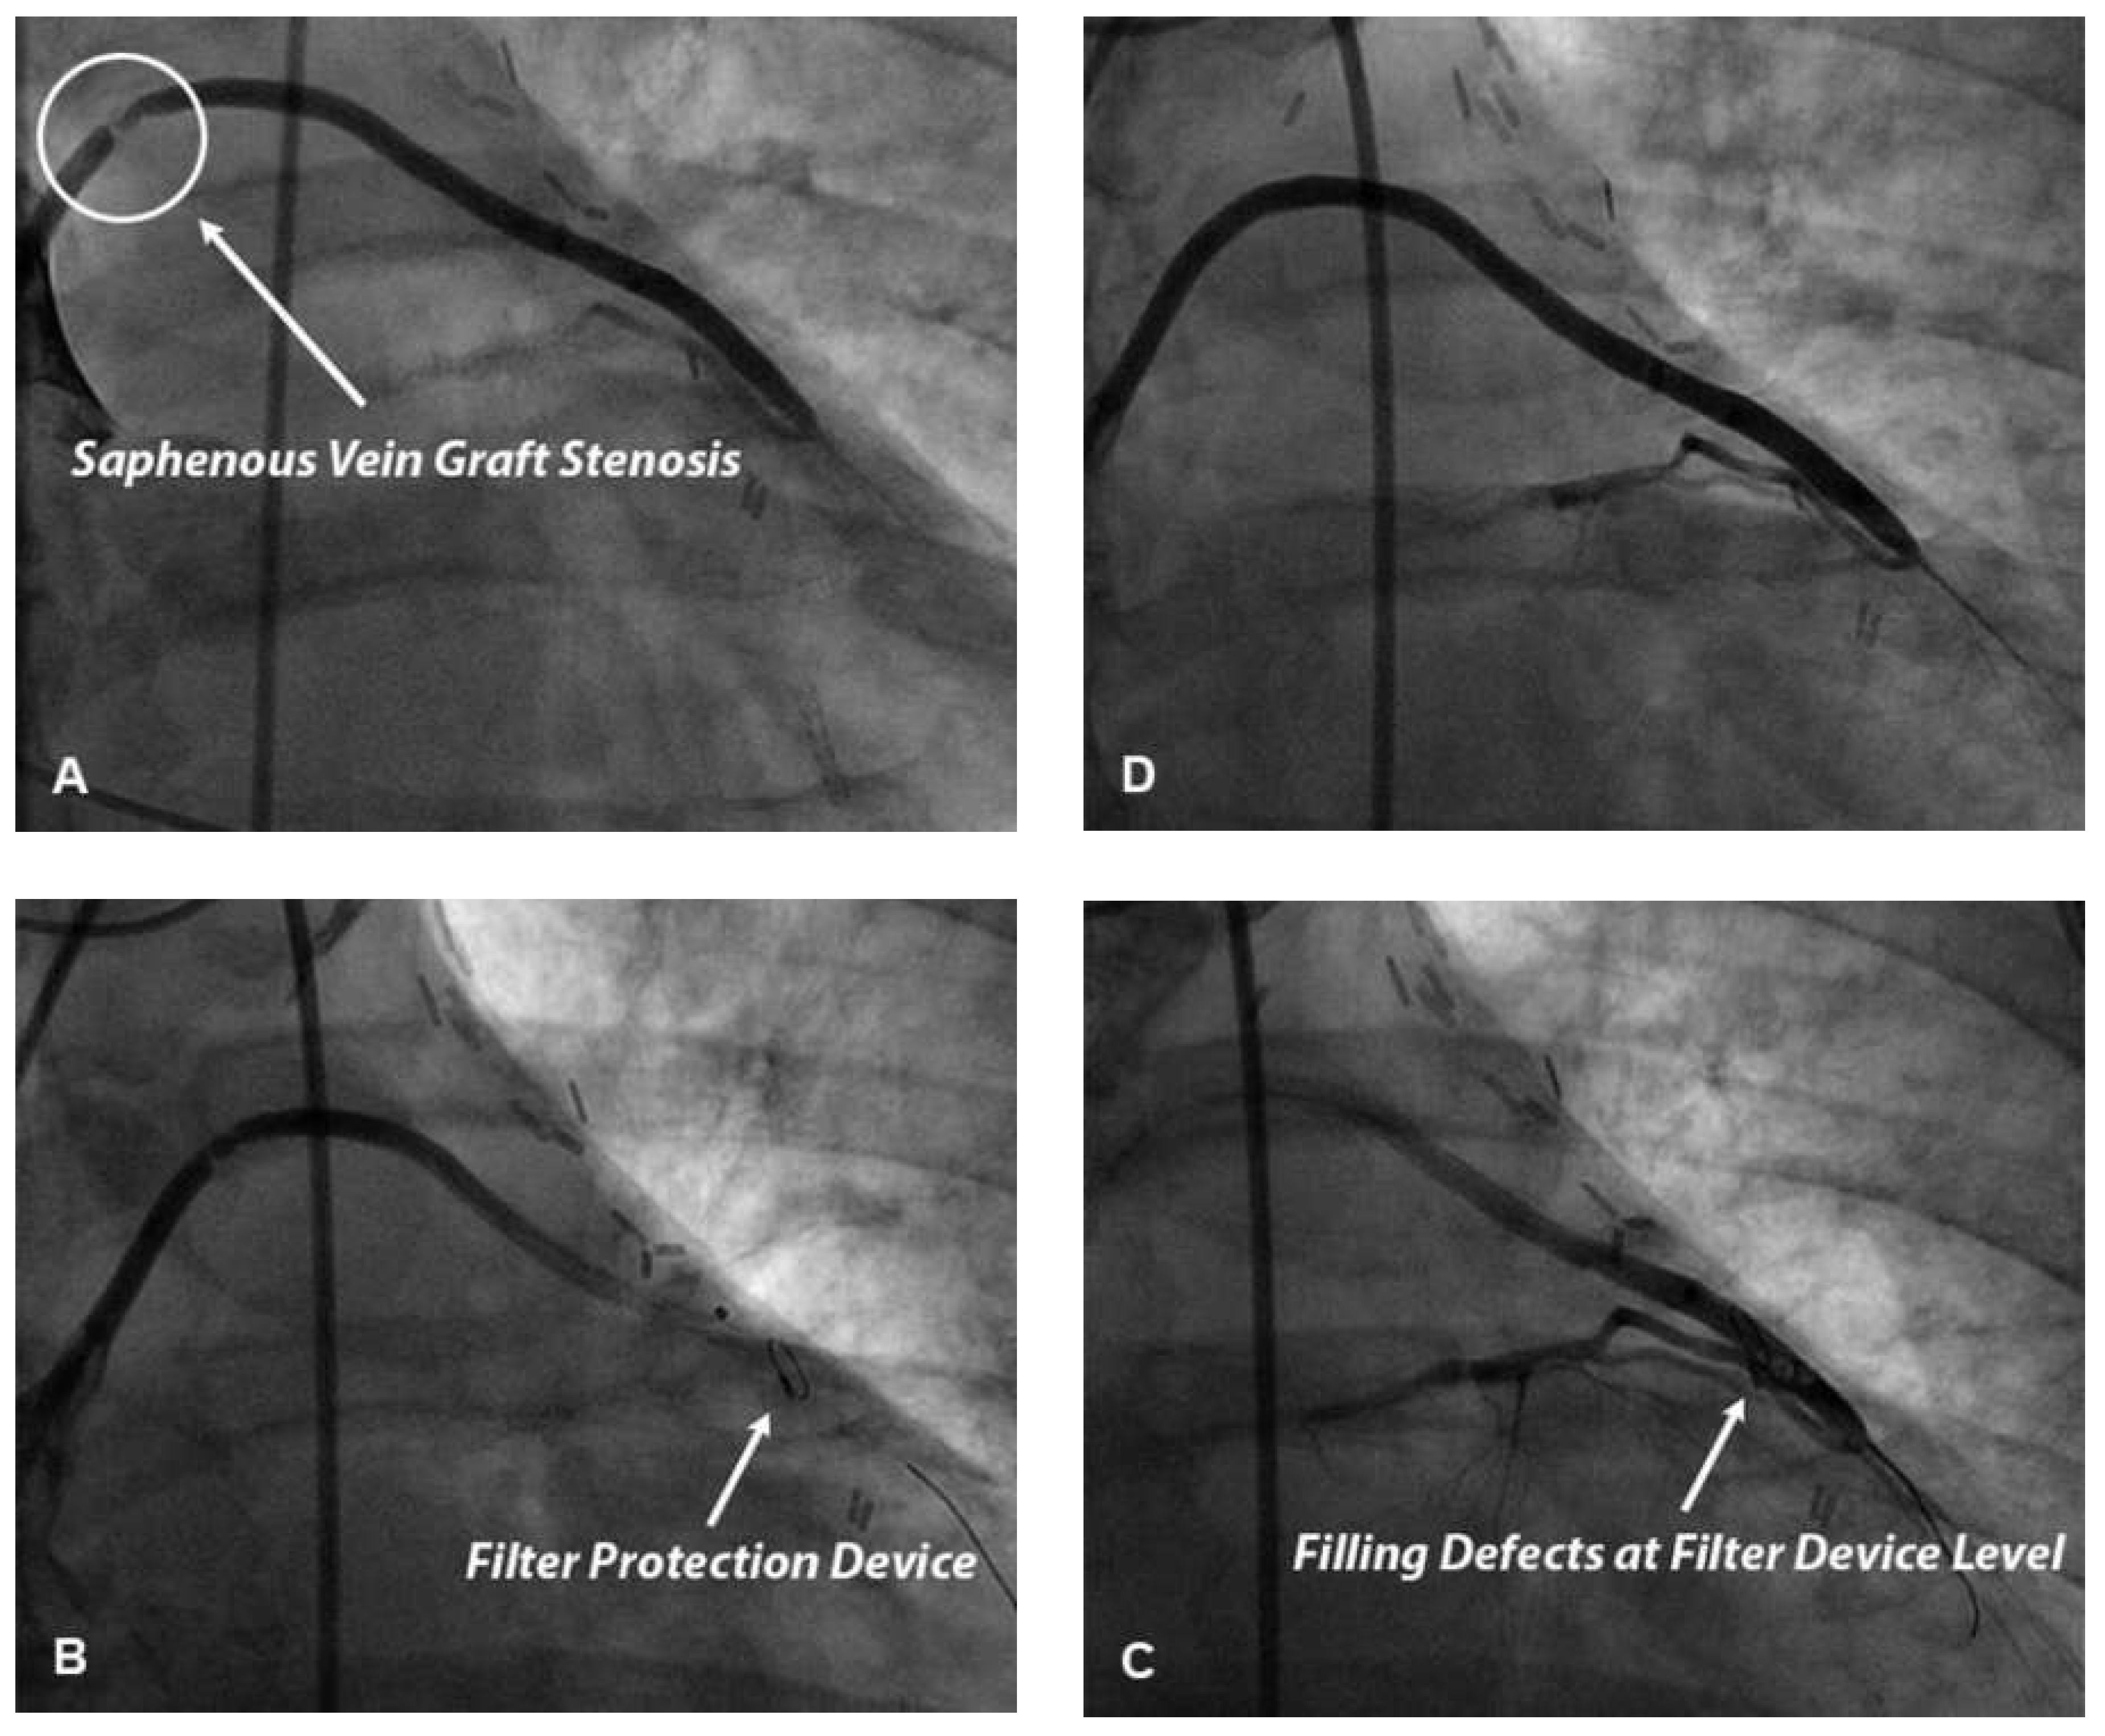

Figure 1. Panel A. Coronary angiography of an 82-year-old smoking, hypertensive and dyslipidaemic patient presenting to the emergency department for typical chest pain. Angiography shows a subocclusive thrombotic lesion of the proximal portion of first marginal artery. Panel B. After guidewire crossing of this thrombotic lesion, a thrombus aspiration catheter was advanced into the mid portion of first marginal artery beyond the thrombus. Panel C. Thrombotic material retrieved from culprit coronary plaque. Panel D. After thrombus aspiration a percutaneous coronary intervention (PCI) was performed. The patient underwent direct stenting with drug-eluting stent implantation. Good final angiographic result with a post-PCI TIMI flow 3.

The use of manual or mechanical thrombectomy devices to reduce the risk of distal embolisation during pPCI has been investigated in several clinical trials. Manual thrombectomy is usually performed using dedicated catheters compatible with a 6 or 7 French guiding catheter on 0.014’’ guide-wires and allows direct retrieval of intraluminal thrombus (Figure 1). Mechanical thrombectomy devices like Angiojet® use high-pressure backward saline jets to create a vacuum at the tip of the catheter to break up and remove thrombus.